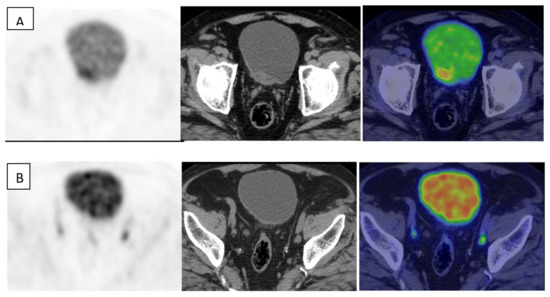

- Ali, S.A.; Abdelkawi, M.M.; Hussien, N.M. Delayed post-diuretic 18F-FDG PET/CT: Can it help in determination of the best clinical decision for muscle invasive UB cancer patients? Egypt. J. Radiol. Nucl. Med. 2019, 50, 1–8. [Google Scholar] [CrossRef]

- Yan, H.; Zhou, X.; Wang, X.; Li, R.; Shi, Y.; Xia, Q.; Wan, L.; Huang, G.; Liu, J. Delayed 18F FDG PET/CT Imaging in the Assessment of Residual Tumors after Transurethral Resection of Bladder Cancer. Radiology 2019, 293, 144–150. [Google Scholar] [CrossRef] [PubMed]

- Harkirat, S.; Anand, S.; Jacob, M. Forced diuresis and dual-phase18F-fluorodeoxyglucose-PET/CT scan for restaging of urinary bladder cancers. Indian J. Radiol. Imaging 2010, 20, 13–19. [Google Scholar] [CrossRef]